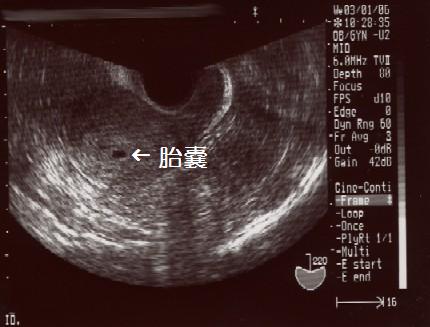

まだあまり特徴のあるおもしろいエコー写真ではありませんが、成長はしています先週の出血以来の受診でドキドキこの1週間は、けっこうゆっくりさせてもらいました。昼から夕方。夕方から夜はダイゴローとまとめて数時間寝たりして今回は吐きづわり・食べづわり・眠たくなるつわり・臭いが敏感になるつわりすべて楽なようです。ダイゴローがいるからかな?一緒に遊んでくれるから、気が紛れているのかな(笑)ダイゴローの誕生日に結構カロリーの高いものを摂ったり、自宅安静で寝てばかりいたにも拘らず体重の増加はありませんでした。やっぱり晩御飯を遅く食べるのが、私の肥満の原因みたいです。元々太りやすい体質で気をつけていたけど、結婚して数十キロ単位で太っちゃったもんなぁ★これからは、ぼん(パパ)なんか待たないで子供と一緒に食べる習慣にしよう血圧は…高目でしたこの先大丈夫かなぁ…おなかが大きくなると、本当に内蔵が圧迫されて苦しいの知ってるから…怖いなぁどうしようもないのかなぁ…先生に相談すると「太らない事・むやみに体重増加しないように」とのこと。今回はキッチリ言ってる意味がわかってま・・・^^;内診の結果は、出血の後も見当たらないし・心拍もよろしいとのこと。とうとう妊娠届の用紙をもらい、第2子の母子手帳をもらいましたやっぱり母子手帳がもらえると安心する。それまでは流産する確立も高いらしいですからね。先生と看護師さんに「おめでとう」の言葉と、「無理するなよ」の優しい言葉をもらいました^^